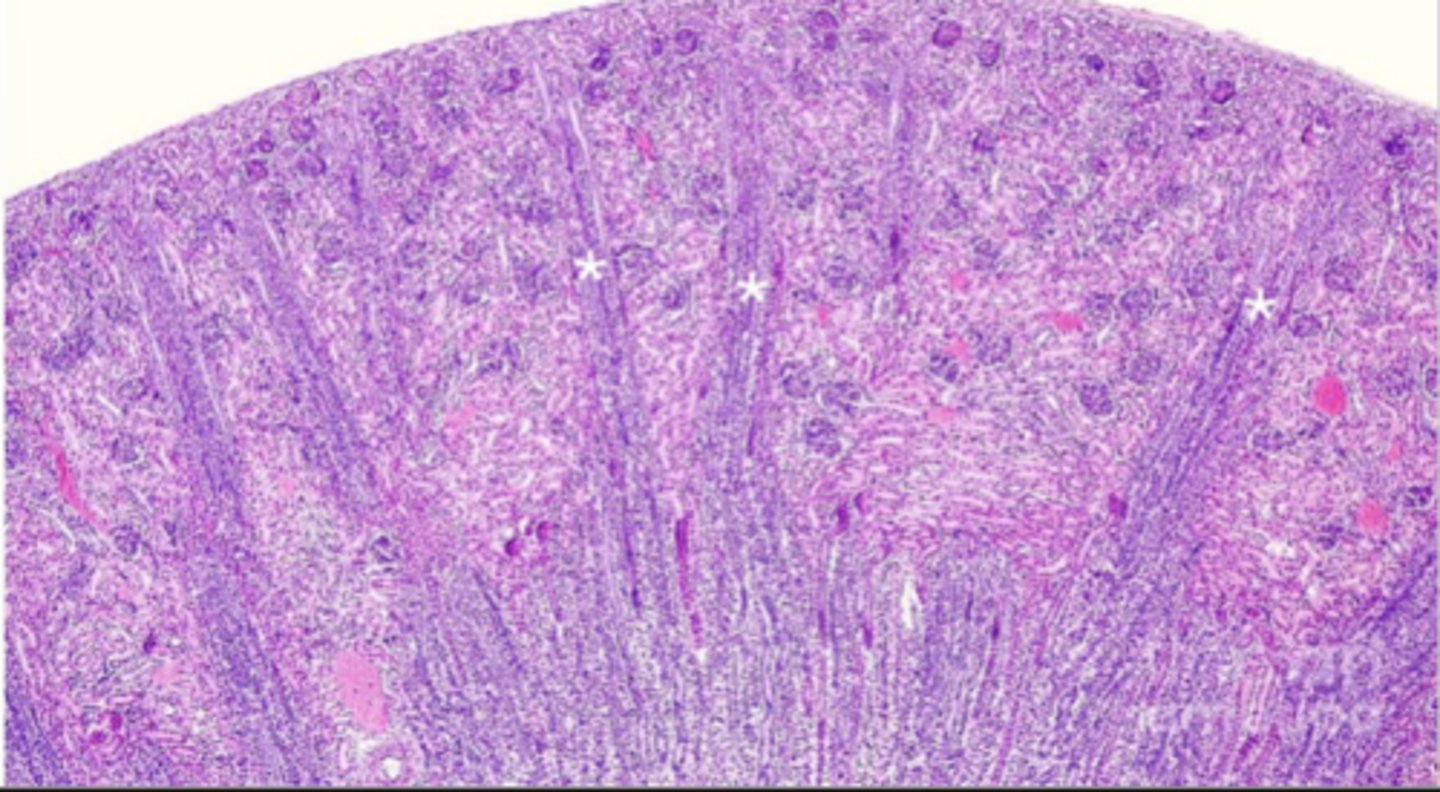

what is in the medullary rays

straight tubules and collecting ducts (green boxes)

what is in the cortical labyrinth

convoluted tubules, and glomeruli

what is in the medullary rays 2

proximal and distal straight tubules

arched collecting tubules and straight collecting tubules

the medullary rays are only in the ___________ of the kidney